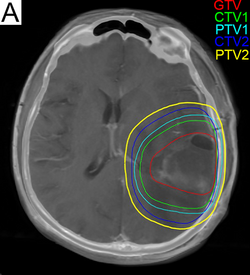

Radiation treatment planning for glioblastoma. GTV: gross tumor volume, CTV: clinical target volume, PTV: planning target volume.

Subsequent to surgery, radiotherapy becomes the mainstay of treatment for people with glioblastoma. It is typically performed along with giving temozolomide.[10] A pivotal clinical trial carried out in the early 1970s showed that among 303 GBM patients randomized to radiation or best medical therapy, those who received radiation had a median survival more than double those who did not.[70] Subsequent clinical research has attempted to build on the backbone of surgery followed by radiation. Whole-brain radiotherapy does not improve when compared to the more precise and targeted three-dimensional conformal radiotherapy.[71] A total radiation dose of 60–65 Gy has been found to be optimal for treatment.[72]